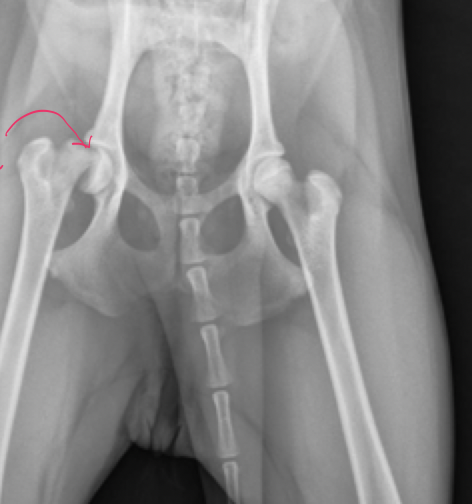

Rt. Femoral Capital Physeal Fracture

muscle atrophy evident on the Rt. leg

Salter harris type 1

delayed physeal closure in early neutered male